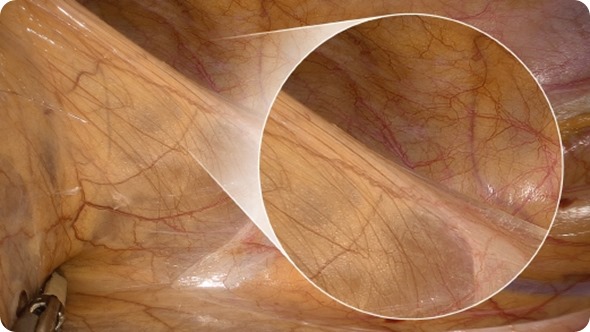

An enlarged color spectrum encompassing around one billion colors is now reality. The system improves the visibility of edges and fine details of delicate tissue, such as blood and lymphatic vessels and nerves. Above all, the richer reproduction of reds assists surgeons in ensuring that incisions are even more accurate.

VISERA 4K UHD: The endoscopy system offers surgeons four times higher resolution to support highly precise surgical procedures

The magnified visualization function allows the surgeon to use the telescope fitted to the VISERA 4K UHD even at some distance from the part of the body being operated on, while still delivering high resolution, sharp images. The remote position of the VISERA 4K UHD also prevents collisions with other handheld instruments.

- Allows surgeons to observe fine patterns and structures of tissues in the body in extreme detail even when enlarged